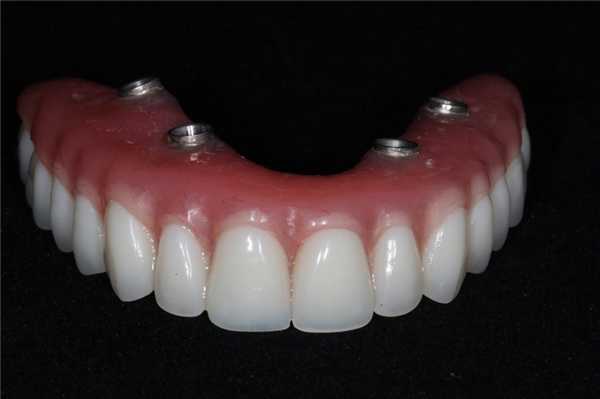

Временный протез функционировал на протяжении 6 месяцев для полной адаптации пациента к внешнему эстетическому виду и новым окклюзионным соотношениям. Окончательная протетическая конструкция состояла из титанового каркаса, покрытого десневым композитом Gradia (GC America), и металлокерамических коронок, зафиксированных поверх титанового базиса (фото 18). Окончательный результат реставрации виден на фото 19.

Фото 18. Вид окончательного протеза через год после первичного вмешательства.